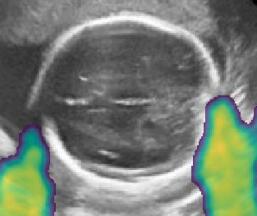

Fig. 6 compares the shadow confidence maps of the state-of-the-art methods and the proposed methods. RW and have the same parameters as used for Table I. The shadow confidence maps of the baseline, the proposed method and the proposedAG method are generated directly from input shadow images by confidence estimation networks. Overall, the proposed method and the proposedAG method achieve more visually reasonable shadow confidence estimation than the baseline and the state-of-the-art on different anatomical structures shown in Fig. 6. The proposed method and the proposedAG method are able to highlight multiple shadow regions while the RW algorithm shows limitations for most cases, especially for disjoint shadow regions.

Row I in Fig. 6 shows a fetal brain image from . The confidence estimation of shadow regions from the baseline, the proposed method and the proposedAG method are similarly accurate since we use fetal brain images to train the confidence estimation networks in these three methods. These outperform [16] and [22]. Rows (II-IV) in Fig. 6 show shadow confidence maps of non-brain anatomy from , including lips, abdominal and cardiac. The baseline failed on unseen data during inference. However, the proposed methods are able to generate accurate shadow confidence maps because of the generalized shadow features obtained by the shadow-seg module. Furthermore, the “Lips” example shows that our method is capable of detecting weaker shadow regions that have not been annotated in manual segmentation. This indicates that the confidence estimation network has learned general properties of shadow regions.